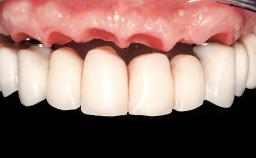

Prosthodontic SAC classification

| Defining Characteristics | - |

| Loading Protocol | - |

| Esthetic Risk | - |

| Occlusion/Articulation | - |

| Occlusal Scheme/Issues | - |